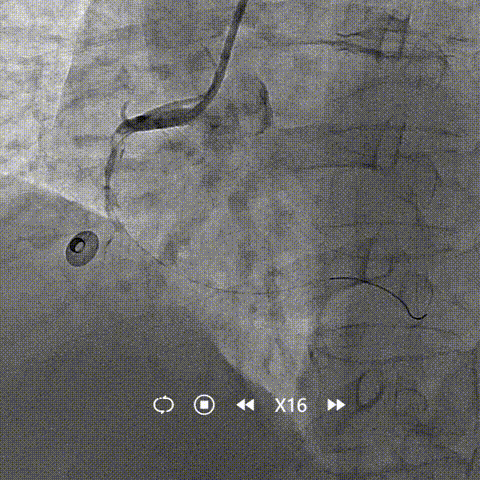

抽吸【例】量|【捷】谈血栓抽吸